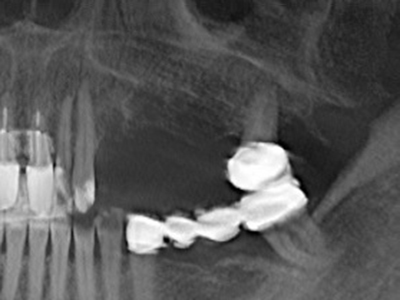

Indication: Sinus lift

Preparation of the lateral window during an external sinus floor elevation is challenging, particularly for implantologists with little surgical experience. Removal of the bone cover of the sinus without injuring the underlying Schneiderian membrane is only part of the operation – after establishing an adequate access, the membranous lining of the sinus must be carefully mobilized to make space for the augmentation materials or the implants. Piezo surgery is useful for this indication in two ways: diamond-coated instruments can be used for selective bone ablation and the underlying mucous membrane remains intact when the procedure is done carefully. The ultrasonic frequencies also enable detachment of the mucous membrane without complications – the frequencies are transmitted into the space between the mucous membrane and sinus floor by special blunt attachments (Cassetta, Ricci et al. 2012, Pereira, Gealh et al. 2014) (Rickert, Vissink et al. 2013). As a result, it is not surprising that current reviews of external sinus floor elevation positively evaluate the use of piezoelectric devices as well as the use of roughened implant surfaces and bone replacement materials (Wallace, Tarnow et al. 2012).